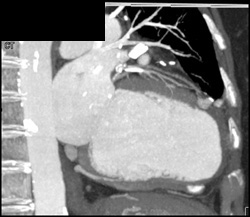

LAD Plaque Seen With MIP Imaging